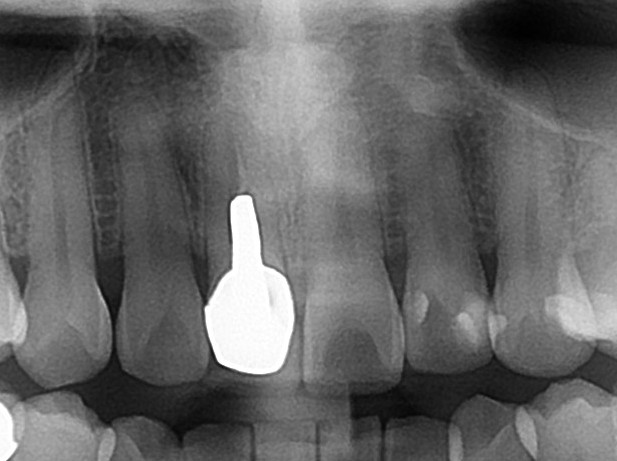

この黒い原因は、レントゲン写真を見ると分かります。

差し歯が埋め込まれています。

青い部分が白く写っており、メタルコアという金属の土台が埋め込まれています。

こちらの歯は神経がもう無いのですが、本来されていないといけない根管治療がされていません。

矢印の箇所ですが、神経のあった根管が黒く写っています。

本来は根管治療がしっかりされていると、材料が入るために白くレントゲン写真で写ります。